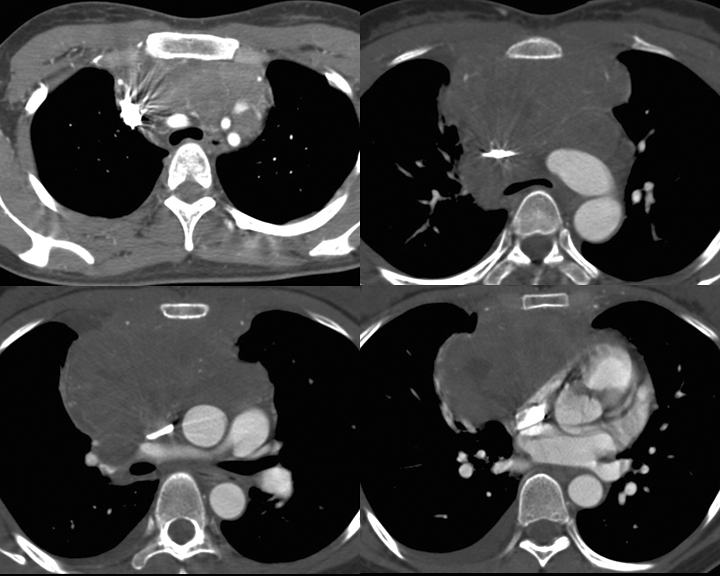

Gallery Mediastinum Lymphoma 7c

7c